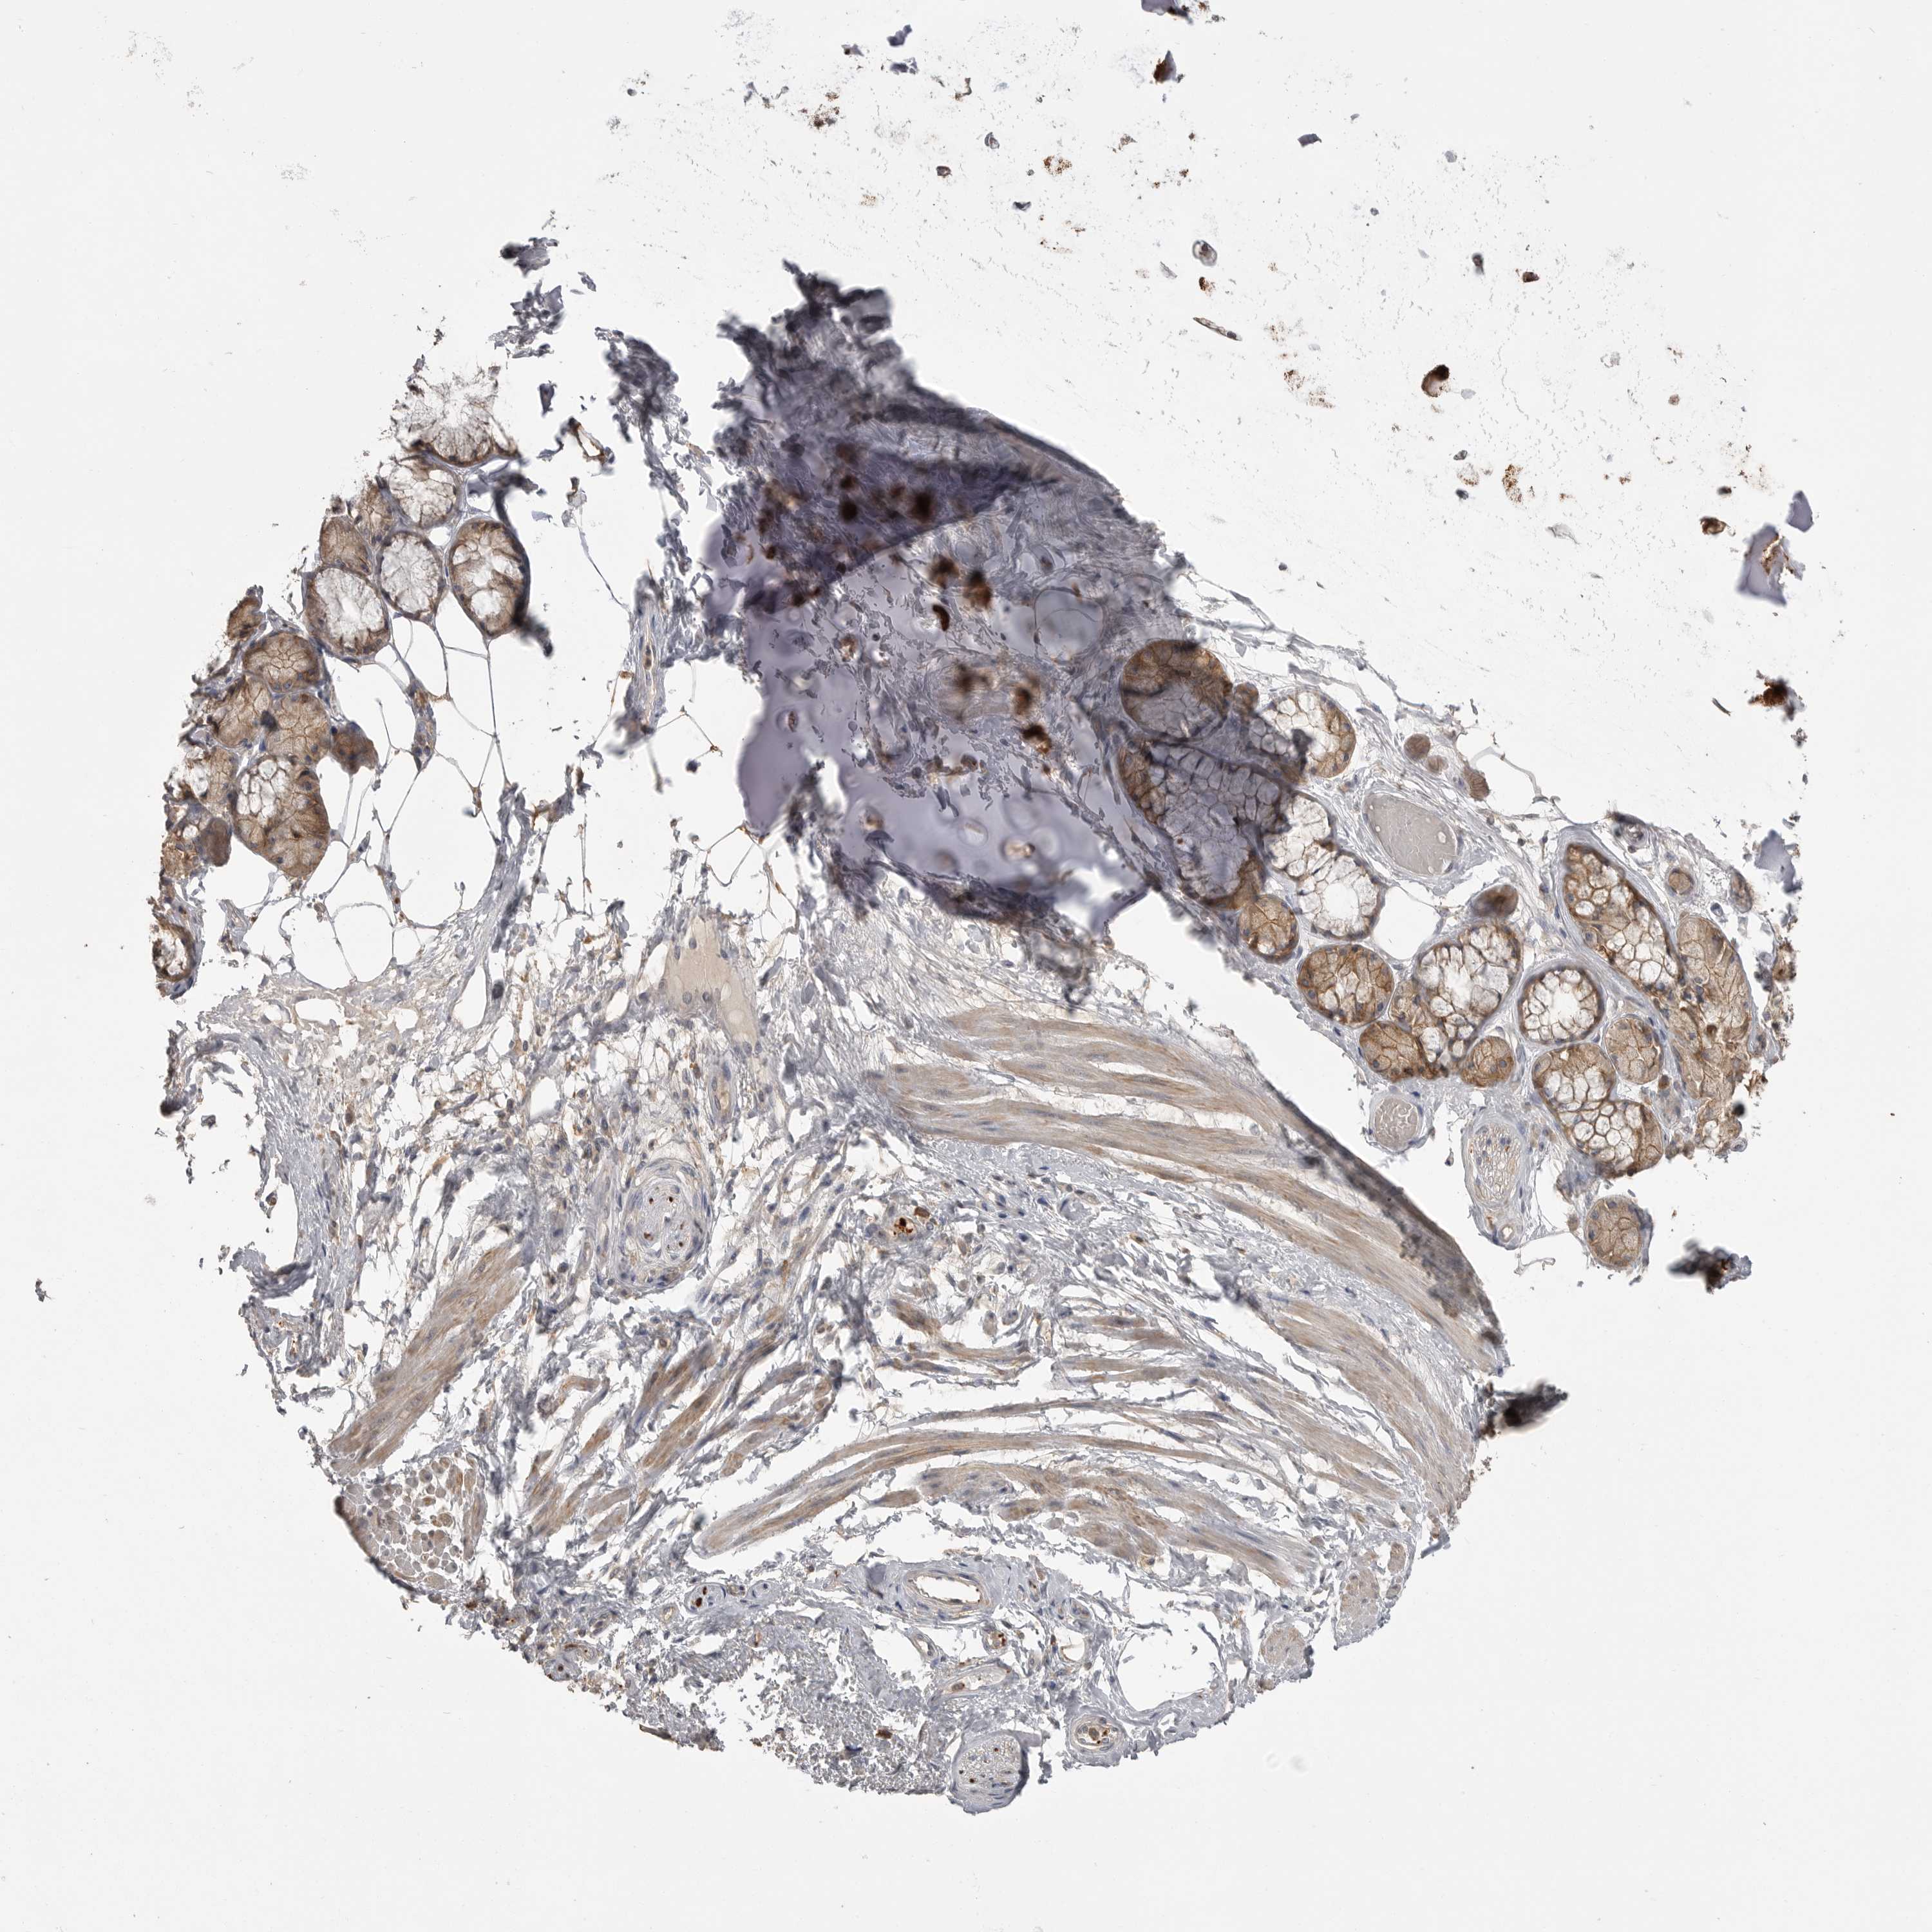

ADIPOSE TISSUE - Antibody stainingi

Antibody staining in the annotated cell types in the current human tissue is reported as not detected, low, medium, or high, based on conventional immunohistochemistry profiling in selected tissues. This score is based on the combination of the staining intensity and fraction of stained cells. Each image is clickable and will lead to virtual microscopy that enables deeper exploration of all samples and also displays staining intensity scores, fraction scores and subcellular localization as well as patient and tissue information for each sample.

Ascending and descending describe two types of gradient, based on difference in staining intensity between enterocytes in crypts and apical enterocytes.

Ascending - the staining intensity is stronger in apical enterocytes (towards the lumen) compared to enterocytes in the crypts (gland based)

Descending - the staining is weaker in apical enterocytes compared to enterocytes in crypts

Antibody HPA026980

Adipocytes Low